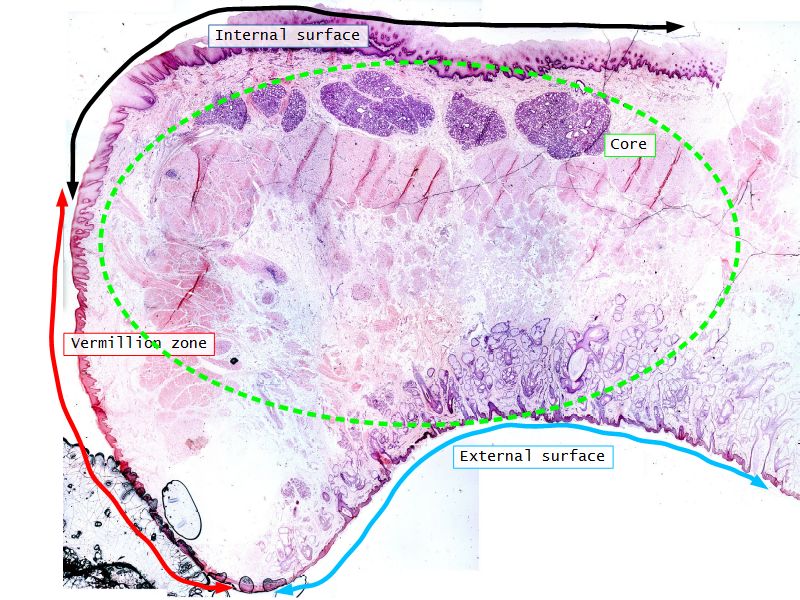

Nipple - slide 15